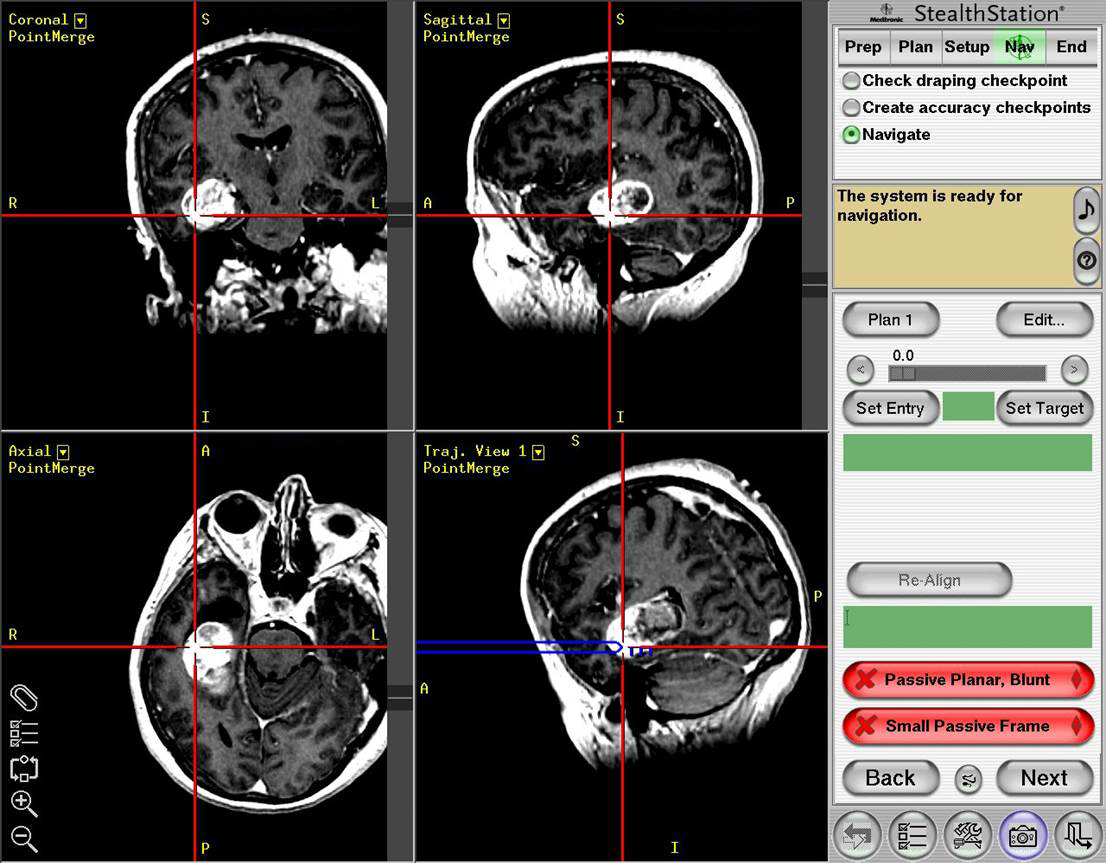

The MR images below show a brain tumor in the right temporal lobe that was found after the patient had a seizure, which is how many brain tumors are first discovered. The lower image demonstrates the stereotactic surgical approach to the tumor (Images courtesy of Dr. McMurtrey)